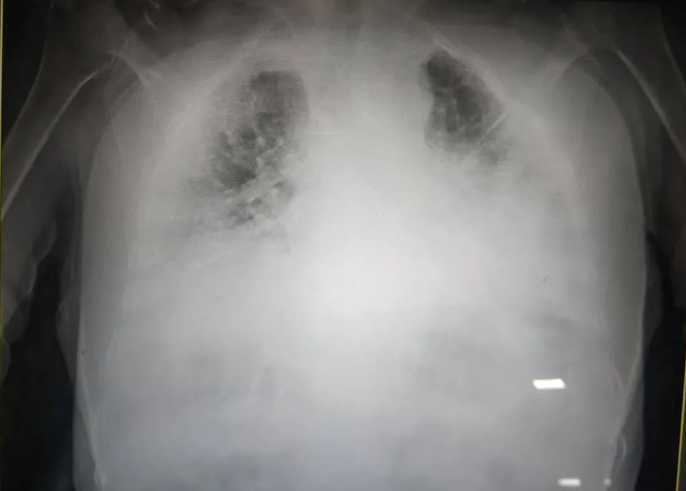

У Львові медики показали, який вигляд мають легені, уражені коронавірусом. Органи на світлині перетворилися на суцільну світлу пляму.

“Це одні з найстрашніших легень, які я бачила в житті”, – зазначила лікарка.